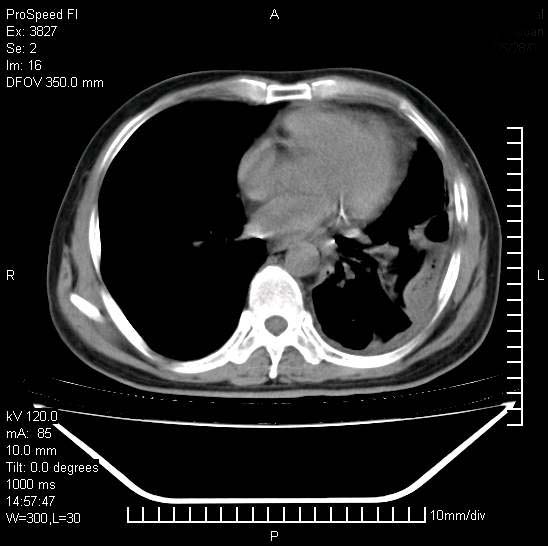

男性,一月前出现右侧肋区疼痛,较剧烈,干咳,无发热,自诉使用抗炎药后缓解,几天前又出现左侧剧烈疼痛,

发热,体温38。9,今天ct,考虑左侧包裹性脓胸,胸腔积液,右上中肺小斑片影,结核/炎症?胸水未见恶性细胞。